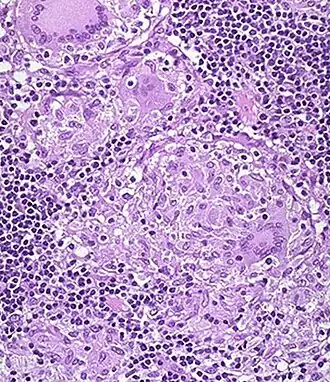

Специфическая гранулёма в стенке толстой кишки.

Микроскопически во всей толще кишки находится воспалительный инфильтрат, состоящий из лимфоцитов, плазматических клеток, эозинофилов. Образуются характерные гранулёмы из эпителиоидных клеток и гигантских многоядерных клеток типа Пирогова-Лангханса. Творожистый некроз в гранулёмах не наблюдается, что сближает их с саркоидозными гранулёмами.